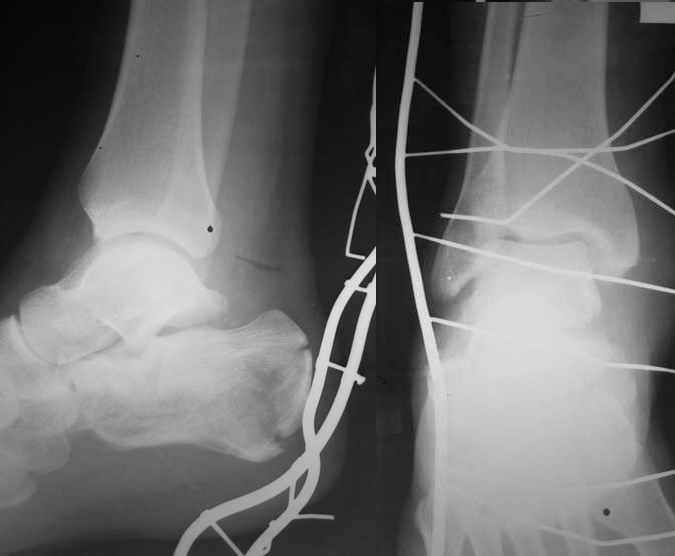

В/суставные переломы пяточной кости у молодых являются показанием к оперативной коррекции, Большой материал накоплен у д-ра Дрягина (Челябинск). В нашем отделении предпочтение отдаем открытой репозиции, при наличии выраженного отека, фликтен и т.д.

Накладываем спицевой дистрактор, позволяющий выхаживать м/ткани и одновременно устранять захождение отломков.

Окончательная фиксация спицами, пяточными пластинами (5) , в последнее время стали применять крючковидные пластины (ДЕОСТ) (6,6a).

Кроме стандартных снимков, необходим контроль конгруэнтности суставной поверхности (проекции Бродена)